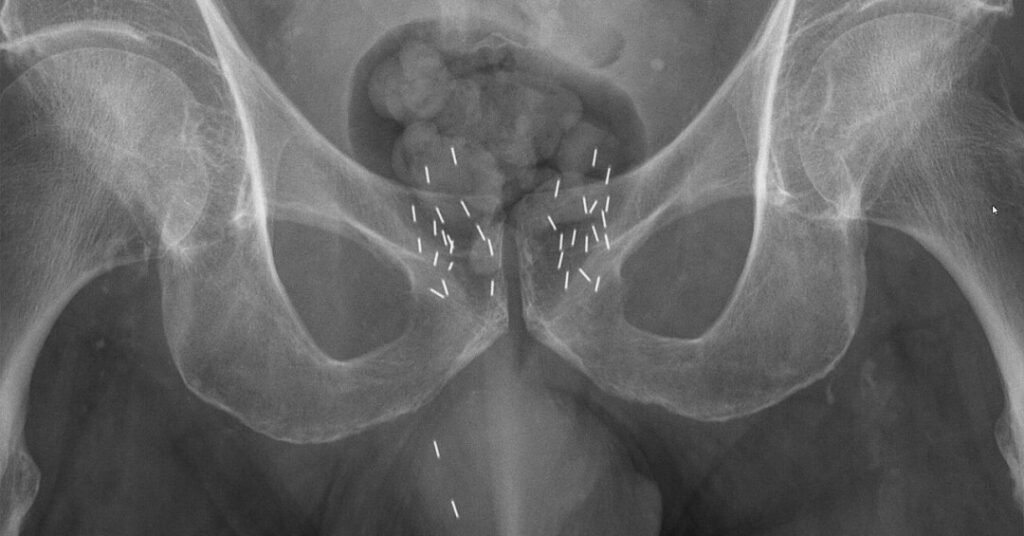

Na braquiterapia, a equipe médica implanta no paciente as chamadas “sementes”: pequenos radioisótopos em cápsulas, emissores de radiação, colocados de forma estratégica nos lugares que são alvo do tratamento.

As sementes podem ser posicionadas dentro do próprio tumor ou em tecidos vizinhos a ele, conforme o caso.

Quando há indicação, a braquiterapia pode ser temporária ou permanente. No primeiro caso, as sementes são levadas até uma área próxima do tumor por meio de cateteres ou outro tipo de aplicador, sendo removidas após as sessões. Já na braquiterapia permanente, as cápsulas são colocados no local desejado por meio de microagulhas, não sendo retiradas posteriormente.

Esse tratamento pode ser indicado para diferentes tipos de câncer, conforme avaliação médica. Tumores de próstata e mama são bons candidatos à técnica permanente. Cânceres na região cervical, de modo geral, também costumam receber esse tratamento.